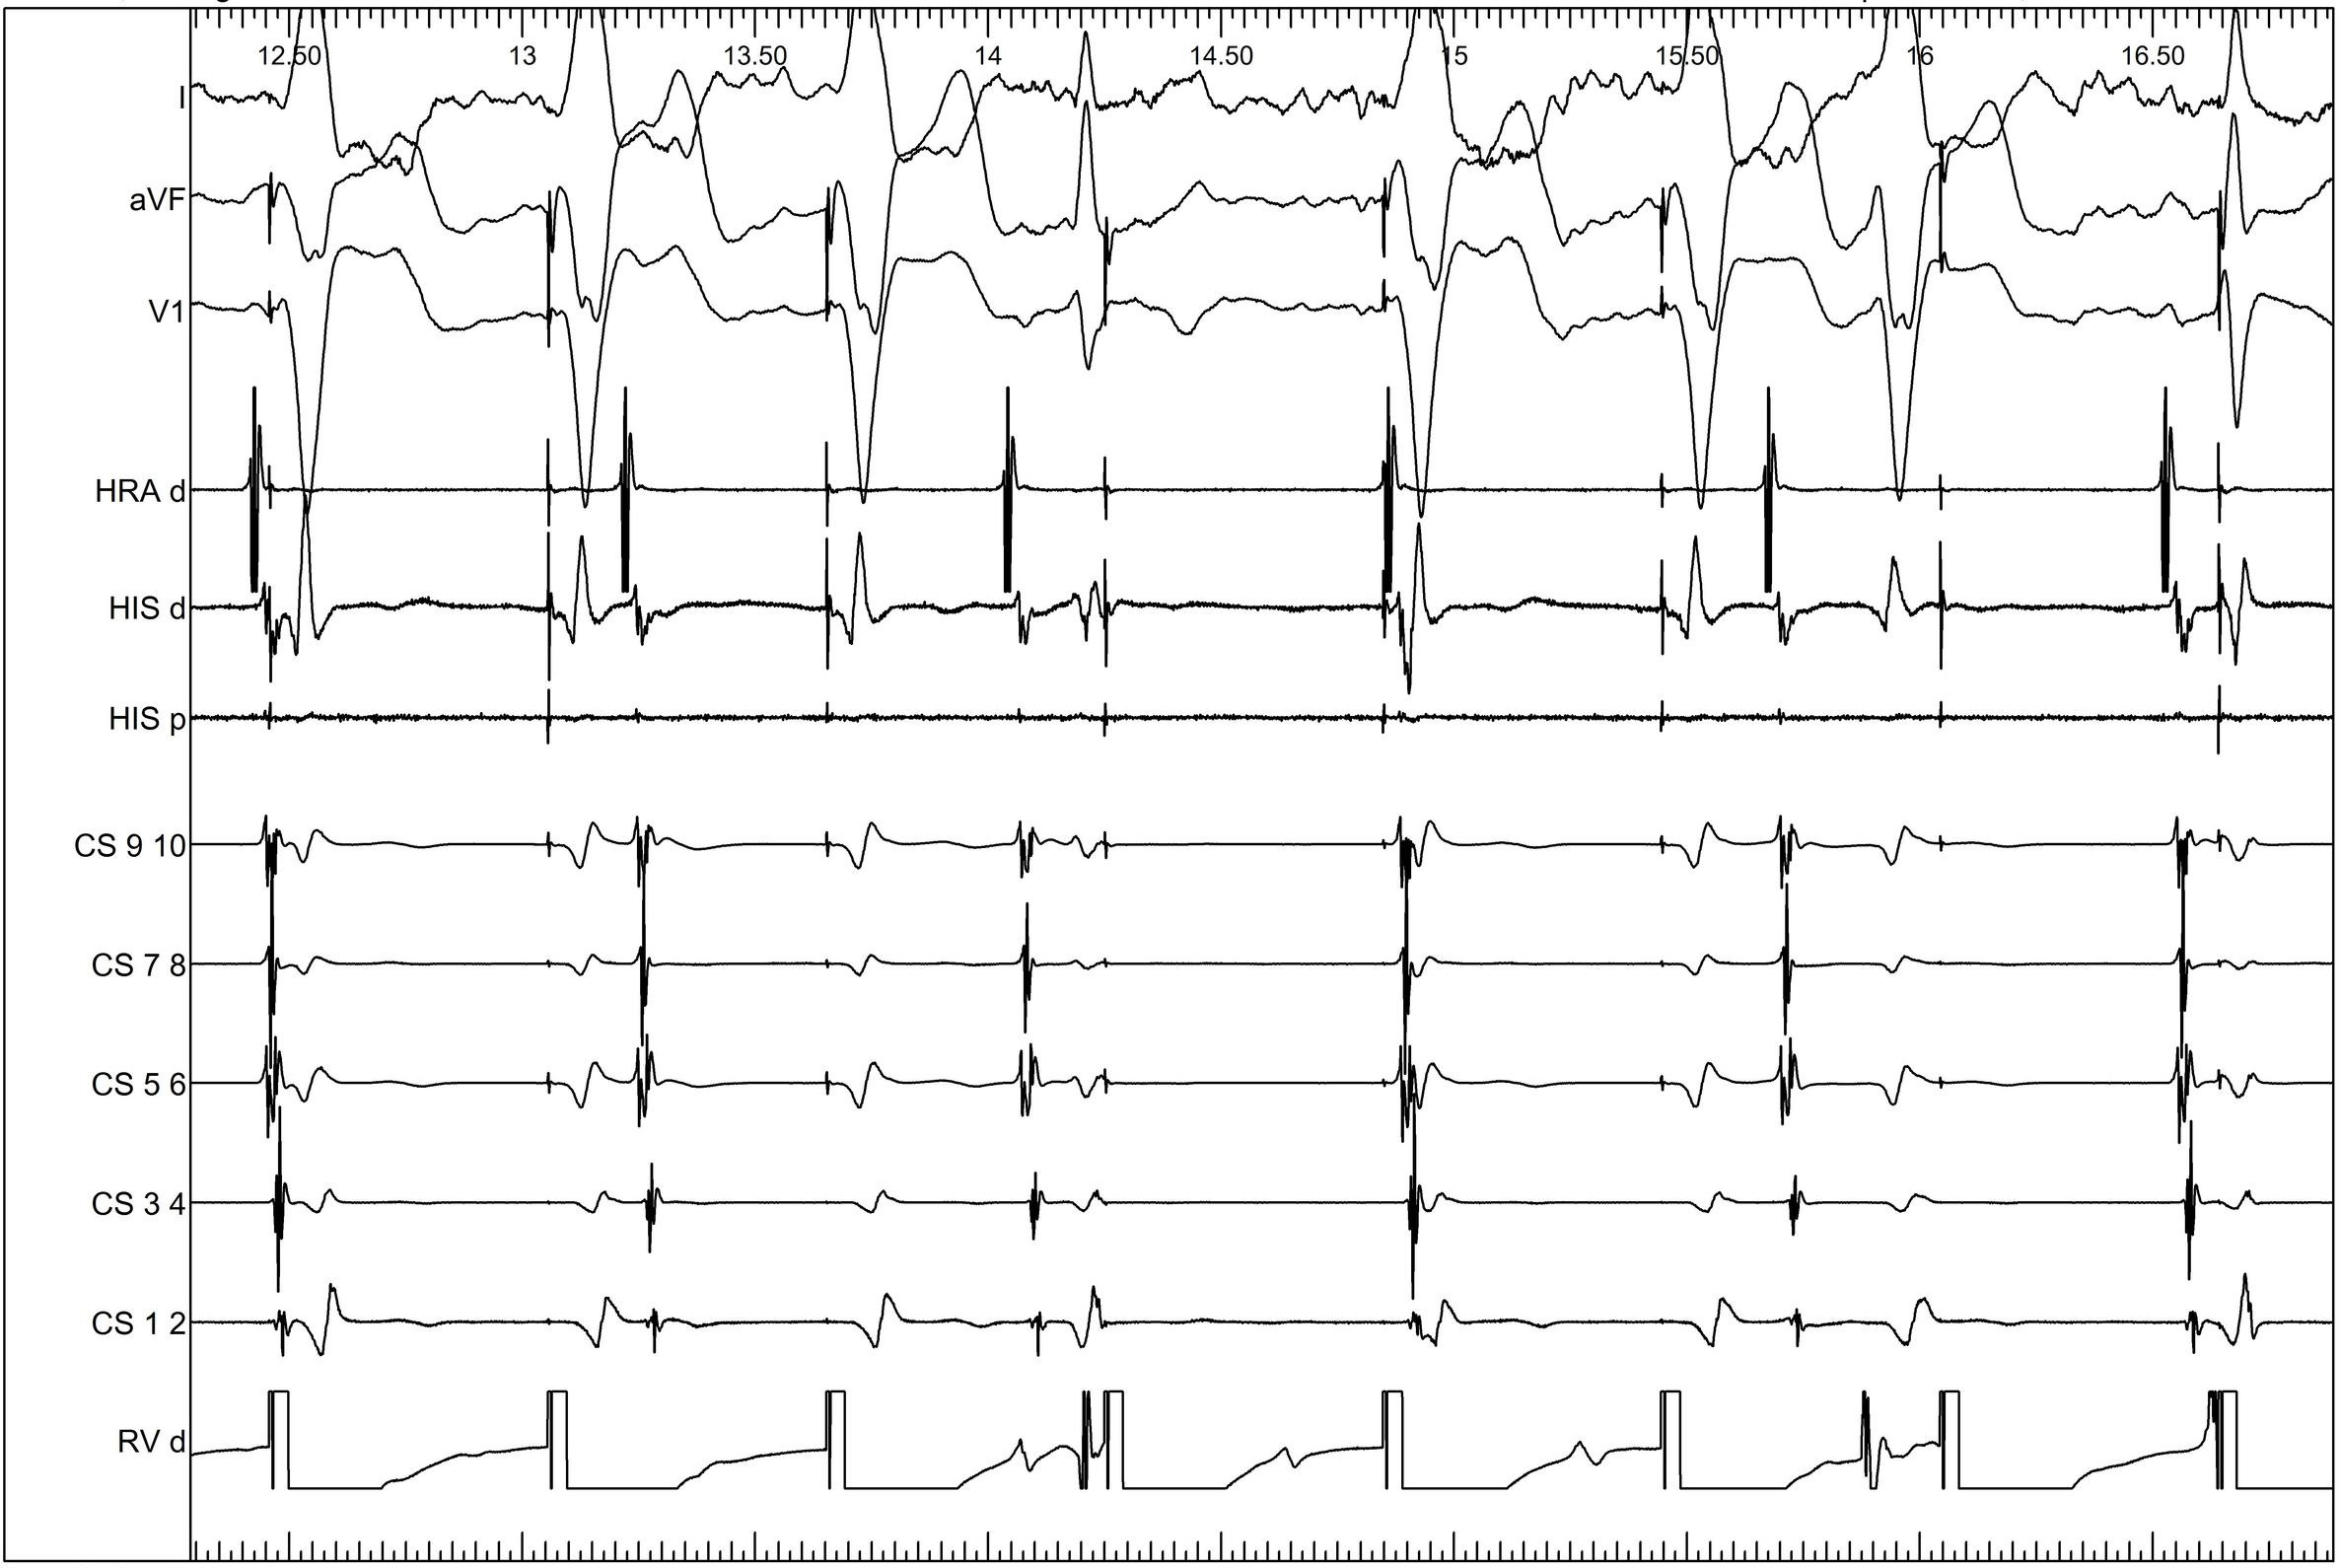

Baseline measurements

01_baseline.jpg